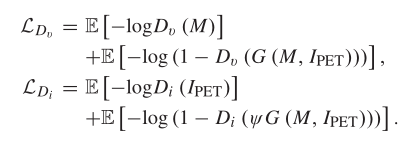

辨别器损失函数

相比生成器来说就简单了,其实就是通过训练使得红外/可视图像辨别器分辨图像是融合图像还是可视/红外图像的能力越来越强。

以可视图像辨别器为例来介绍

这里第一项希望Dv可以把可视图像源图像v识别为可视图像的概率越大越好,即logDv越大越好,-logD越小越好;第二项则是希望Dv可以将融合图像G识别为可视图像的概率越小越好,即Dv(G)越小越好,1-Dv(G)越好越好,-(1-Dv(G))越小越好。第二项同理。

辨别器损失函数